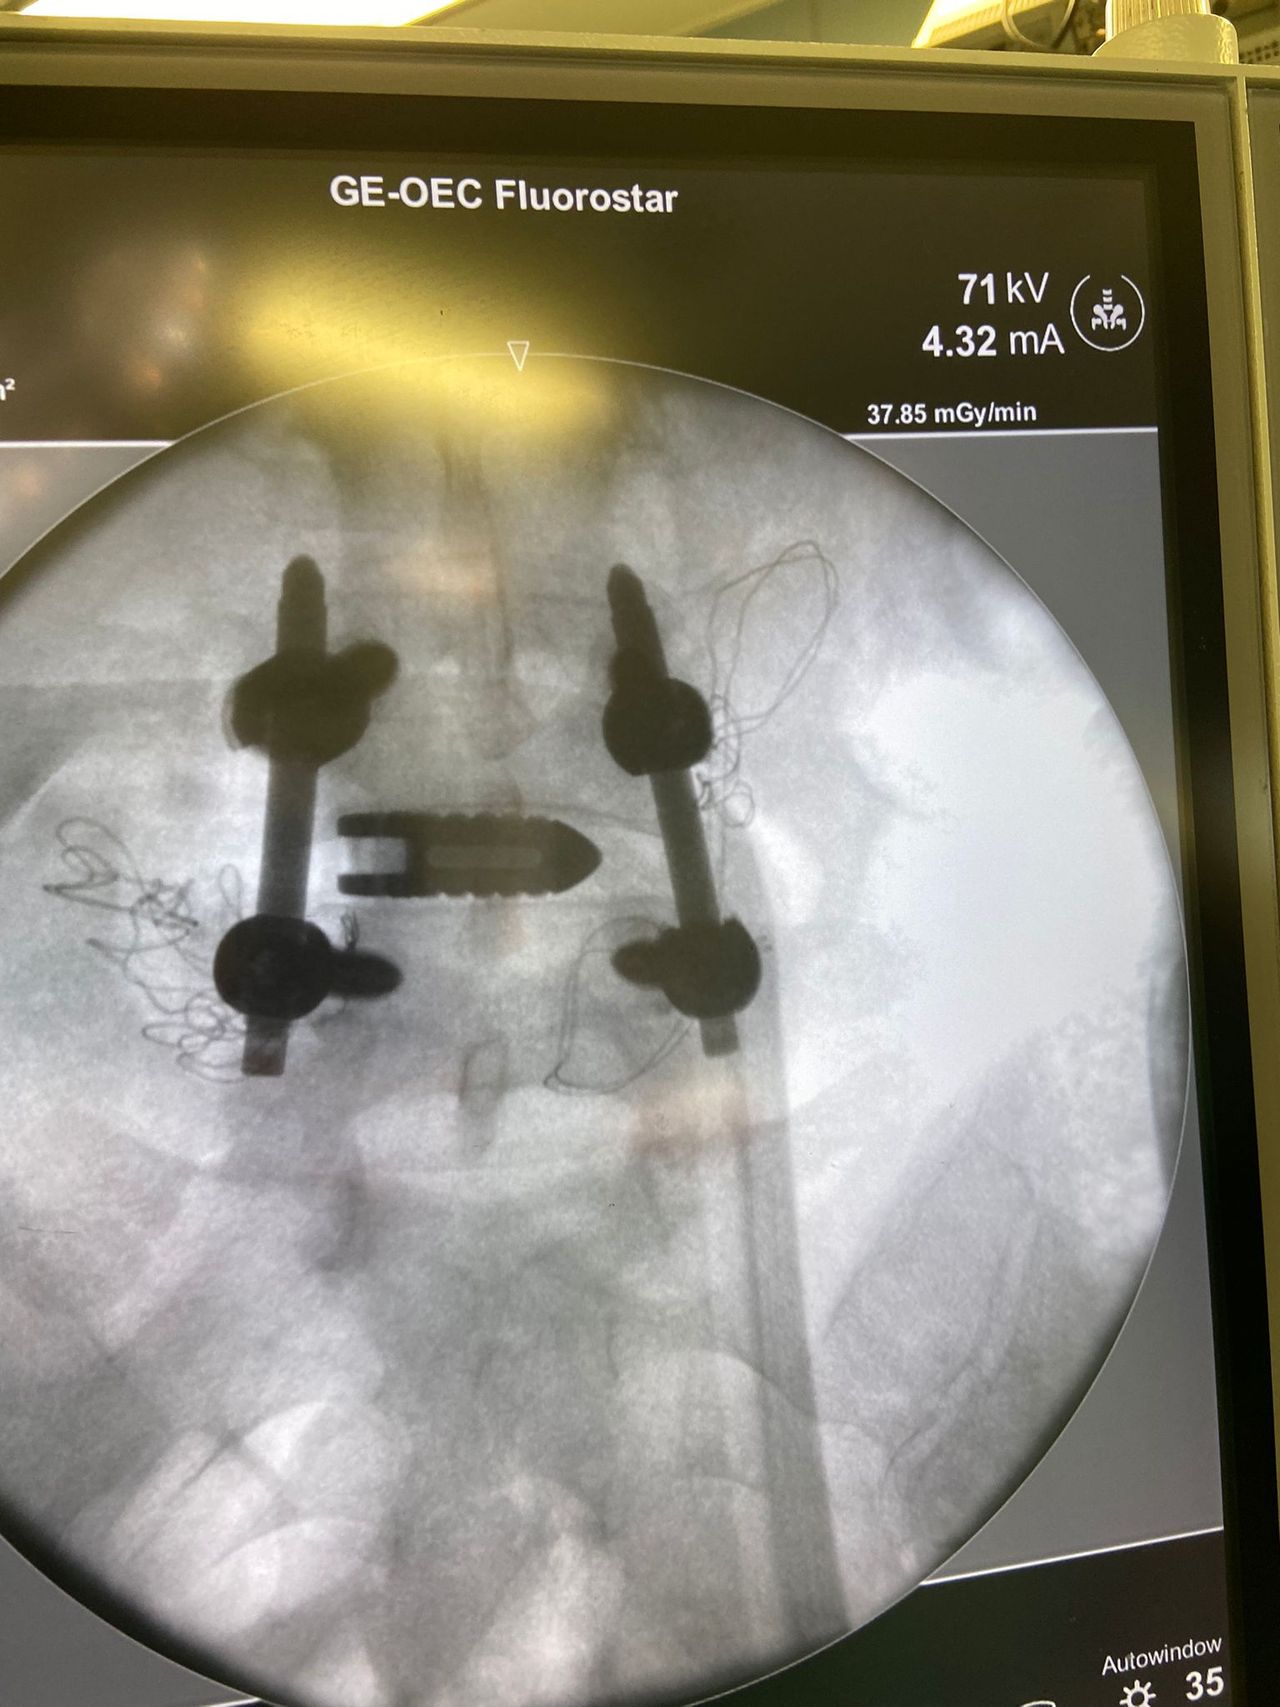

Foto e video